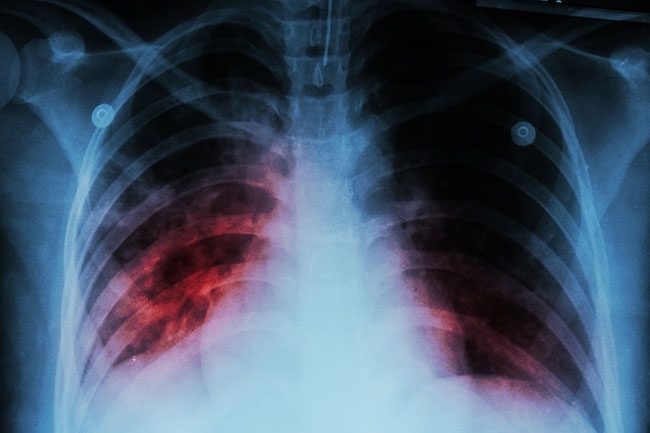

От 23 до 27 юни 2025 г. в Силистра ще се проведат безплатни прегледи за туберкулоза в рамките на националната кампания "Седмица на отворените врати", организирана от Министерството на здравеопазването. Инициативата е част от Националната програма за превенция и контрол на туберкулозата, която цели ранна диагностика и намаляване на заболеваемостта от това социалнозначимо заболяване.

По време на кампанията всеки желаещ ще може да премине анонимна оценка на риска чрез анкета и консултация с медицински специалист. При установяване на повишен риск, ще бъдат назначавани допълнителни изследвания. При доказани случаи се предприемат незабавни мерки за лечение и прекъсване на веригата на заразяване.

Според данните от предходни кампании (2022–2024 г.), близо 15 000 души са се възползвали от прегледите в страната, като над 4000 от тях са били насочени към химиопрофилактика или лечение. През 2024 г. България отчита най-ниското ниво на заболеваемост от туберкулоза – 13,7 на 100 000 души.